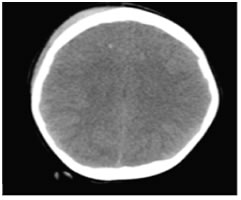

SECONDARY LESIONS

- diffuse cerebral edema

- Cerebral edema is mainly divided into two categories;

- Cytotoxic and

- Vasogenic edema.

- Interstial/ combined

- Due to traumatic effect the ATP dependent Na/K pumps fails and leads to increase in the water content within the cell due to osmotic gradient leading to cytotoxic edema25.

- On the other hand, vasogenic edema occurs as a resultof disruption of the blood-brain barrier, such as in intracranial hematoma secondary to head trauma, brain tumours or infection. Water moves from the vasculature to the extracellular space in response to an osmotic gradient25,26.

- Imaging findings of diffuse cerebral edema on CT; diffuse cerebral parenchymal hypoattenuation and loss of normal differentiation gray and white matter (Fig 14), effacement of sulci, perimesencephalic and suprasellar cistern, compression of ventricular system4,25,26.

Figure 14: Axial NECT scan: A 7-year old boy who was found while hanging on Parenchymal low attenuation, effacement in sulci and loss of differentiation gray and white matter indicated to diffuse cerebral edema.